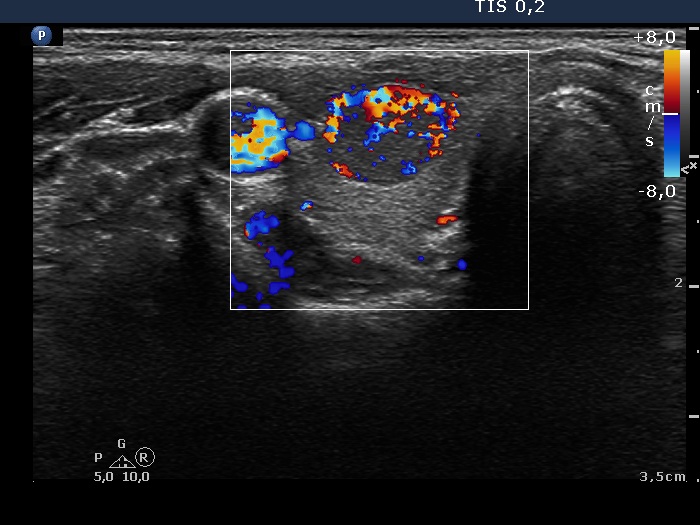

Ultrasonography. The thyroid was echonormal and presented a moderately hypoechoic nodule in the right lobe and a cystic nodule with minimally hypoechoic solid part corresponding to the previously aspirated cystic lesion. The largest diameter of the latter was 11 mm which means that cyst has not refilled. The nodule in the right lobe showed irregular, more hypoechoic areas all along at the periphery. This pattern mimicked halo sign, but indeed the lesion did not have a real halo. The vascularization of the nodule in the right lobe presented an irregularly increased intranodular blood flow while the lesion in the left lobe did signs of perinodular vascularization.

Second examination 3 years later (second row of images)

Ultrasonography. Both the pattern and the size of the nodule in the right lobe remained unchanged. The cystic content of the left lobule has disappeared, it was replaced by inhomogeneous solid part. The vascularization of this lesion has also changed, the intranodular vascularization has become significantly increased.